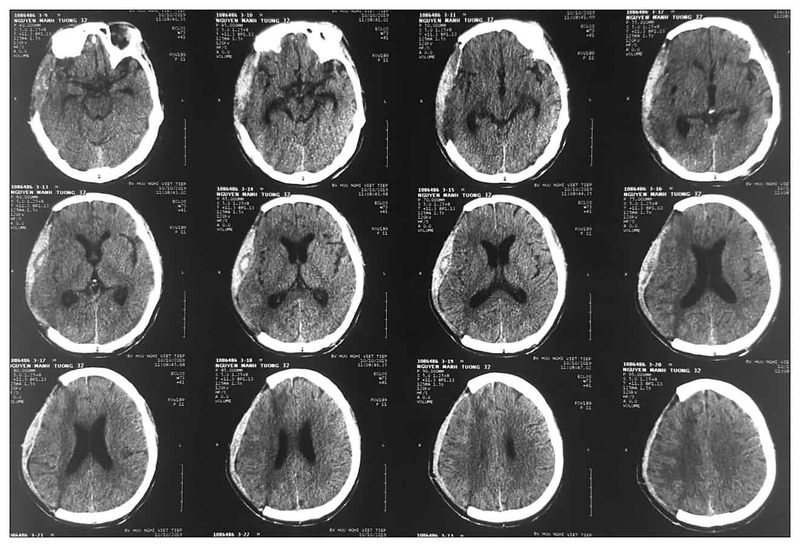

Phẫu thuật tụ mủ dưới màng cứng không phải là một phẫu thuật cấp cứu đơn giản và cần được thực hiện bởi bác sĩ có tay nghề cao. Đặc biệt ở người cao tuổi, triệu chứng lâm sàng của tụ mủ dưới màng cứng mạn tính rất dễ nhầm lẫn với các bệnh lý như đột quỵ, mất trí nhớ, do đó người bệnh cần được khám lâm sàng kỹ lưỡng và chẩn đoán hình ảnh sớm để có chẩn đoán chính xác và can thiệp phẫu thuật kịp thời.